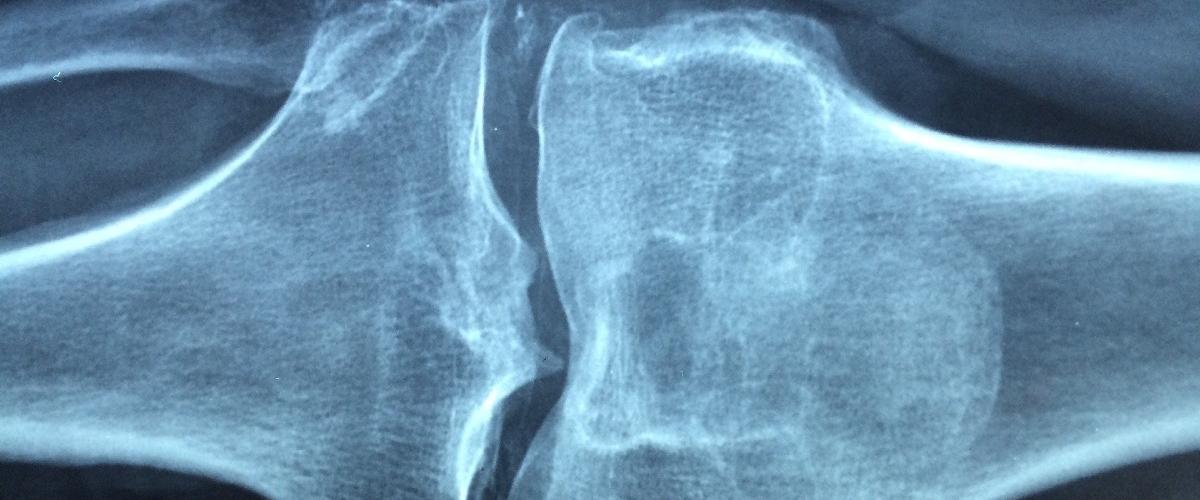

В здоровом состоянии организм постоянно заменяет поврежденные костные ткани, обеспечивая должные качество и массу костей. Остеопороз, нарушение обмена веществ, приводит к потере способности организма формировать новую костную ткань и разрушать или удалять старые ткани. По данным Фонда здоровья костей и остеопороза (BHOF), каждая вторая женщина и каждый четвертый мужчина за 50 ломает кость по вине этого заболевания.